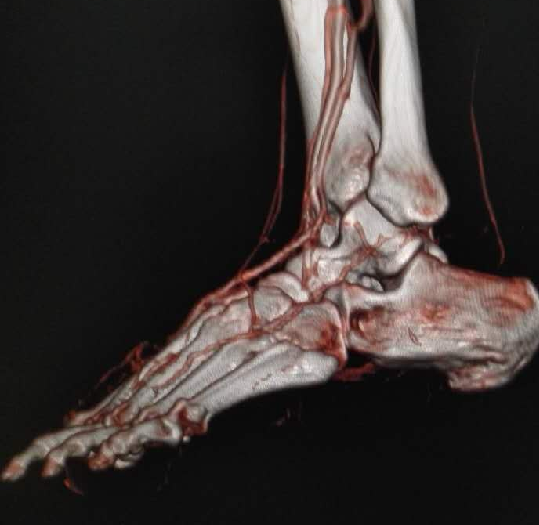

多年来,贵州航天医院各科室紧跟医学前沿,不断强技术、补短板,大力开展新技术、新项目,完成了许多高精尖、高难度、本地区“首例”的技术,填补了医院医疗技术空白,满足了群众日益增长的医疗需求。 贵州航天医院骨科率先在遵义地区开展骨搬移技术,截至目前,已治愈慢性骨髓炎、感染性骨不连、骨缺损、脉管炎、糖尿病足患者200余例,糖尿病足治疗保肢率达到98%。 本期,我们将为大家带来骨科特色技术——骨搬移技术(Ilizarov)。 案例分享 一名59岁的患者,身患糖尿病12年,在来我院3个月前出现了右脚溃烂的症状,来院就诊时,患者的右脚十分红肿,右脚脚趾坏死,伤口处不断流出黑红色脓液,情况十分严重。在接诊到患者时,骨科专家团队高度重视,立刻为患者完善了CT血管造影(CTA)等相关检查,诊断为:2型糖尿病,糖尿病周围血管病变,右糖尿病足。 术 前 考虑到患者情况比较严重,为最大限度保证患者肢体完整,科室专家团队进行了严格的讨论评估,为患者制定了骨搬移技术治疗方案,在征得患者及其家属的同意后,成功通过搬移骨块为患者进行治疗,促进患者病变肢体血管再生。 胫骨横向骨搬移外架固定 清除感染病灶 术后调节外架,通过搬移骨块 促进患肢血管再生 患者在术后三周前来换药,观察到感染得到进一步控制;术后六周复查,患者病变处已愈合,进行CT血管造影(CTA)后可明显观察到足部血管再生。 术后3周 术后6周愈合 CT血管造影见足部血管再生 糖尿病患者全身与局部的问题互为影响,形成恶性循环,糖尿病足溃疡创面迁延不愈,常见干性坏疽、湿性坏疽、趾坏死、深且大的溃疡以及骨髓炎等症状,还可导致脓毒血症,以往为保全生命,患者被迫选择一次或多次截肢。骨搬移技术的发展进步,能在血糖有效控制、局部有效清创下,有效促进患肢微血管再生,改善患肢血供,达到糖尿病足更快治疗康复的目的,并能根据病变情况最大限度的保障患者肢体完整。 什么是骨搬移技术 骨搬移技术是通过使用专用的骨外固定器固定骨段,每天缓慢牵拉,在牵拉搬移过程中,骨段尾部形成新骨及新的软组织,从而修复骨骼缺损及软组织缺损。是治疗大段骨缺损、骨不连、骨感染、肢体畸形的金标准方法,也用于治疗脉管炎、糖尿病足等肢体缺血性疾病。 骨感染缺损 切除感染段 搬移骨段 新骨形成 骨感染根治愈合 骨搬移技术原理 生物组织在持续、稳定、缓慢牵拉下,能刺激细胞分裂、组织再生,骨外固定技术运用该原理,通过持续缓慢调节外固定器形成牵拉张力,促进牵引成骨与相邻组织再生,如神经、血管、肌肉、皮肤等再生,达到治疗大段骨缺损、肢体缺血如糖尿病足等疾病的目的。 骨搬移技术优势 (一)除治疗骨缺损、骨不连外,有更广的适用范围,利用组织再生、血管再生等特性,能大量运用于肢体畸形的矫形、糖尿病足等的治疗。 (二)治疗效果确切,重建肢体外型和功能,极大降低截肢率和残疾率。 (三)明显提高了患者生活质量,极大减轻其家庭及社会负担。 肢体畸形的矫形 慢性骨髓炎 骨段切除 术后1年 濒临截肢的脉管炎术后6周 难愈创面术后3周 贵州航天医院骨科 专家团队 赵学平 骨科主任 主任医师 临床擅长:从事骨科临床工作30余年,对骨科常见疾病的诊治具有丰富的临床经验。 世界中医药联合会脊柱康复专业委员会常务理事,中华中医药学会整脊分会常务委员,中国中西医结合学会骨伤科分会肢体矫形功能重建与康复专家委员会常务委员,中国研究性医院学会骨科创新与转换专业委员会关节外科学组保髋工作委员会常委,中国康复技术转化及发展促进会骨外科与康复技术转化专业委员会常务委员,泛珠三角区域运动医学联盟(PPRD-SMA)理事会常务理事,中国研究型医院学会运动医学专业委员会委员,贵州省中医药学会整脊分会副主任委员,贵州省中西医结合学会银质针专业委员会副主任委员,贵州省康复医学会骨与关节专业委员会常务委员,贵州省人民医院骨科专科联盟常务理事,贵州省康复医学会骨内科专业委员会常务委员,中华医学会贵州省骨科学会委员,贵州省康复医学会脊柱脊髓专业委员会常务委员,贵州省运动医学分会委员,贵州省康复医学会骨与软组织肿瘤专业委员会委员,遵义市医学会创伤分会副主任委员,贵州省康复医学会骨内科专业委员会遵义地区分会常务委员,遵义市医疗事故鉴定、伤残鉴定、工伤鉴定、司法鉴定专家。 长期从事骨科临床研究及教学工作,在国家级、省部级杂志发表论文20余篇,SCI论文2篇,参与主编骨科专著2部,主持省部级科研项目2项,参与指导省部级、市级科研项目6项。 陈明勇 骨科副主任 副主任医师 临床擅长:从事创伤骨科工作约20年,对骨缺损、骨不连、骨肿瘤、肢体畸形等的肢体矫形重建及功能重建,慢性化脓性骨髓炎的根治治疗、糖尿病足的保肢治疗、快速康复理念(ERAS)下的老年骨折的诊治,四肢复杂骨折的诊治,四肢骨折等微创手术治疗具有丰富的临床经验。 2004年毕业于遵义医学院临床专业,曾在中国人民解放军总医院、广西医科大学第一附属医院、上海第六人民医院骨科进修。中国中西医结合学会骨伤科专业委员会横向骨搬移治疗糖尿病足及微血管网再生学组首届委员,遵义市医学会创伤分会常务委员。 瞿 辉 骨科 副主任医师 临床擅长:对骨科的常见病、关节外科、脊柱外科及运动医学疾病的诊治具有丰富的临床经验,熟练掌握骨科手术操作技术。 毕业于遵义医学院临床医学系,2005年前往广州中山大学第一附院骨显微医学部进修学习,2011年前往成都华西医院进修学习,并多次在省内外学习骨科相关知识,是中华医学会骨科分会会员。 赵兴东 骨科 主任医师 临床擅长:擅长骨科的常见病及各种创伤、四肢骨折创伤修复、骨感染、手足疾病的诊治和手足体表畸形的矫形整复,熟练掌握骨科四肢骨病及创伤的手术操作技术,尤其在四肢关节复杂性损伤、手足外伤、组织缺损创面、难治创面的皮瓣修复方面及平足、高弓足矫形方面及四肢慢性疼痛诊治、康复方面具有丰富的临床经验。 硕士研究生,毕业于遵义医学院临床外科系,2015年前往山东省立医院手足外科进修学习;遵义市医学分会创伤分会第一、二届委员,遵义市手外科医学会第二委届员会常务委员;在省级及省级以上期刊发表文章9篇,参编著作2部,参与主持并完成市级课题1项,参与市级课题2项、省级课题1项。 张俊凯 骨科 副主任医师 临床擅长:从事骨科临床工作28年,对创伤骨折、骨感染、骨缺损、骨不连等外科诊治,四肢骨折的微创手术治疗,四肢复杂骨折(如关节内粉碎性骨折、多发骨折等)的损伤控制及手术治疗等具有丰富的临床经验。 1995年毕业于遵义医学院临床专业,2009年前往复旦大学附属医院骨科进修1年。 卢懿明 骨科 副主任医师 临床擅长:从事骨科工作18年,对创伤骨折、四肢骨折的微创手术治疗、四肢复杂骨折(如关节内粉碎性骨折、多发骨折等)的损伤控制及手术治疗,尤其是髋部骨折的PFNA等微创技术,踝关节骨折、膝关节周围骨折的Mipo微创技术等具有丰富的临床经验,开展了4项新技术,发明6项新型专利技术。 2005年毕业于遵义医学院临床专业,2017年,前往南方医科大学第三附属医院骨科进修半年,回院后运用Mipo技术对骨干骨折及干骺端骨折的治疗技术,同时积极开展骨盆骨折、髋臼骨折腹直肌外侧切口的应用;发表了多篇专业论文,经常参与省内外学术交流会授课,获得医院荣誉称号多个。 邬夏荣 骨科 副主任医师 临床擅长:从事骨科工作16年,对四肢复杂骨折、骨肿瘤的诊治,尤其是足踝创伤、慢性踝关节损伤、平足症等诊疗具有丰富的临床经验。 2006年毕业于遵义医科大学临床医学专业,曾在陆军军医大学西南医院进修学习,发表多篇骨科学术论文。 余德怀 骨科 副主任医师 临床擅长:从事骨科工作10余年,对运动医学、骨关节、脊柱外科常见病、多发病的诊治具有丰富的临床经验。 硕士研究生,2011年毕业于遵义医学院临床医学专业,曾前往遵义医科大学附属医院运动医学专业进修学习;是贵州省医学会运动医学分会青年委员,西部关节镜联盟委员;发表多篇骨科学术论文。 冯 乾 骨科 副主任医师 临床擅长:从事骨科工作近20年,熟练掌握骨科多发病及常见病的诊治,尤其对脊柱退变性疾病的诊断及治疗具有丰富的临床经验,主要研究脊柱微创相关治疗方式,能熟练开展椎间孔镜及VBE。 曾前往北京大学第三医院进修学习疼痛及椎间孔镜、首都医科大学友谊医院专业进修脊柱内镜;是贵州省康复医学会第三届脊柱脊髓专业委员会委员;发明专利3项、发表脊柱外科专业论文多篇。 张艳金 骨科 副主任医师 临床擅长:从事骨外科工作16年,对复合伤、多发伤的救治、四肢骨干骨折、关节周围骨折、骨肿瘤、骨髓炎等诊治具有丰富的临床经验。 中共党员,硕士研究生,2006年本科毕业于山西医科大学第二临床医学院,2011年研究生毕业于北京军区总医院;在“老年COPD患者合并髋部骨折的诊治”国际合作课题组研究两年,在老年髋部骨折的诊治方面具有丰富的经验,并发表论文6篇;承担遵义市级课题1项;承担遵义医科大学的临床教学工作,获得遵义医科大学优秀带教老师荣誉。编撰有《骨科疾病诊疗精粹》一书,开展2项新技术,编撰地方规范《务川自治县创伤骨科常见疾病诊疗规范》一书。 赵小锋 骨科 副主任医师 临床擅长:从事骨科临床工作11年,对骨科常见病、多发病诊疗有较为丰富的临床经验,擅长脊柱相关疾病诊断及治疗,尤其是颈、腰、腿疼痛疾病诊断及治疗,擅长胸腰椎骨折微创经皮穿刺内固定术、经皮穿刺椎体成形术、经皮穿刺脊柱内镜下腰椎间盘摘除术、单纯开创腰椎间盘摘除术、腰椎滑脱复位椎间植骨椎融合内固定术、腰椎管狭窄减压融合内固定术及人工髋、膝关节置换术等。 2012年毕业于遵义医学院外科学专业硕士研究生,2019年参加“遵义市115医学人才精英计划”于上海交通大学第一附属医院培训学习,2023年于北京大学第三人民医院脊柱外科进修学习,曾获得遵义市优秀医师荣誉称号。 遵义市手外科第一届委员,遵义市医学会创伤分会第一届委员,遵义市医学会创伤分会第二届委员,贵州省康复医学会第三届脊柱脊髓专业会委员,遵义市医学会烧伤与整形外科学分会委员,发表论文5篇,其中国家级核心期刊1篇,SCI论文1篇,主持市级课题1项并结题,参与市级课题2项。 贵州航天医院骨科简介 基本情况 贵州航天医院(原3417医院)骨科组建于1968年,前身是以创伤和断肢(断指)再植闻名于世的上海市第六人民医院骨科,中国断肢(断指)再植的奠基者、中科院院士陈仲伟等著名专家、学者多次莅临科室指导医疗、教,是贵州省最早拥有专业骨科技术科室之一,在70年代开展了贵州省首例断肢(断指)再植手术。组建50余年来,诊治患者已逾百万,挽救了无数的伤病员,成为了保障遵义地区人民群众健康的重要支撑。 经过几代人的不懈努力,今天的骨科,已由创伤骨科发展至骨病、骨肿瘤、骨结核等领域,现有脊柱外科、关节外科、四肢创伤、手足外科四个亚专科,成为了集医疗、教学、科研于一体的综合学科,是贵州省临床重点专科、遵义市临床重点专科、遵义市骨科临床医学中心、遵义市基层骨科专科联盟理事长单位。 科室目前开放床位110张,共有医护人员50余人,副高级以上专家18人,硕士研究生15人。拥有一流骨科医疗设备多台,每年不定期选派优秀技术骨干到全国各大知名医学院校进修、学习、参观、交流,并邀请国内、国外知名专家教授来院进行交流、指导,通过不断引进国内外先进的诊疗技术,科室医疗技术水平稳步提升,为广大人民群众提供了优质的医疗服务。 专科特色 骨一科 (一)骨缺损、骨不连的肢体与功能重建 胫骨横向骨搬移技术治疗糖尿病足: (二)慢性骨髓炎的根治治疗 (三)肢体缺血性疾病如糖尿病足、脉管炎的保肢治疗 (四)皮瓣修复 (五)复杂创伤的治疗 (六)老年髋部骨折及小儿骨折快速手术 老年髋部骨折: 骨二科 (一)胸腰椎骨折微创经皮椎弓根螺钉固定术 (二)老年性骨质疏松性患者腰椎滑脱脊柱内固定术(骨水泥螺钉) (三)V形双通道脊柱内镜技术(VBE)腰椎融合术治疗腰椎退行性疾病 (四)老年性骨质疏松性骨折(PVP/PKP)术 (五)人工髋关节置换术 (六)双侧股骨头坏死人工全髋关节置换 (七)右侧全髋置换术后假体周围骨折翻修 (八)人工膝关节置换术 (九)人工膝关节假体松动翻修 (十)关节镜技术 传统手术切口 关节镜技术切口 诊疗范围 骨一科 1.四肢创伤、矫形。 2.手、足踝外科。 骨二科